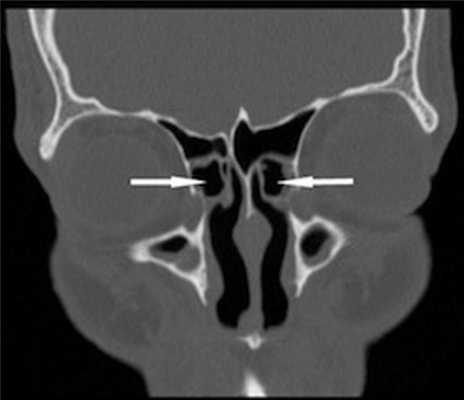

(Слева) На аксиальной КЛКТ (реконструкция) у этого же пациента определяется гипоплазия верхнечелюстных пазух. Обе сфеноидальные пазухи ИЯ выглядят рудиментарными, что сопоставимо с их выраженной гипоплазией.

(Справа) На корональной КЛКТ (реконструкция) у этого же пациента определяется выраженное недоразвитие обеих сфеноидальных пазух. Гипоплазия/аплазия сфеноидальных пазух встречается реже, чем решетчатых или лобных.